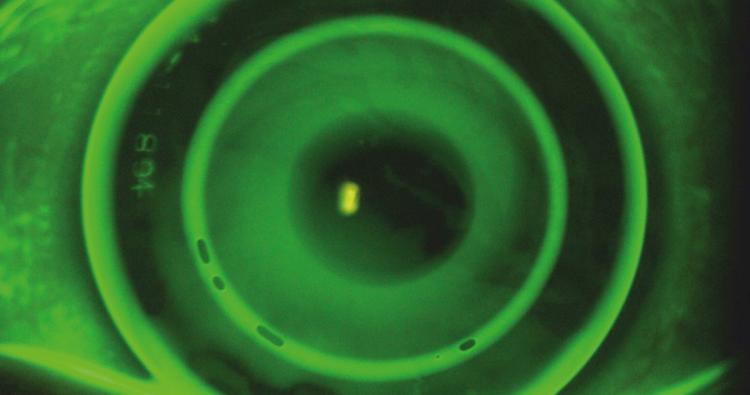

Die Juli/August-Ausgabe der OCL behandelt das Thema Orthokeratologie. Auf dem Titelbild zu sehen: ein Fluoreszeinbild der multifokalen Ortho-K.